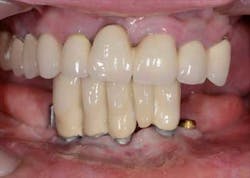

Figs. 1a and 1b: Initial situation of the 61-year-old female patient

Maxillary arch: crown and bridgework collapsing from 3 through 11 and the missing teeth in the upper left are replaced with a partial denture. All the remaining teeth are doomed to extraction.